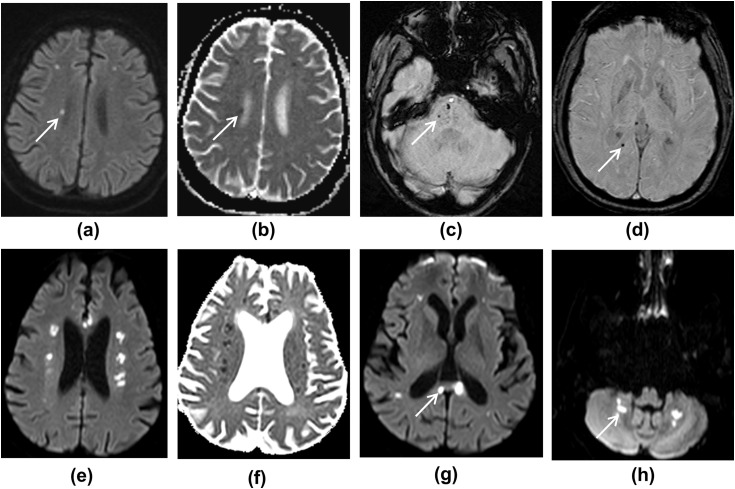

Figure 2.

(a–d) MRI images showing deep watershed white matter hyperintensities with microhaemorrhages. (a) DWI shows multiple foci of high diffusion signal in the white matter, and (b) ADC map shows corresponding low ADC. (c,d) SWI images show foci of microhaemorrhage in the pons, right parietal white matter, and right side of the splenium of corpus callosum. (e–h) MRI images from another patient. (e,f) DWI and ADC images showing multiple deep watershed white matter hyperintensities, suggestive of acute infarcts. (g,h) DWI images show white matter hyperintensities in the corpus callosum and dentate nuclei of the cerebellar hemispheres, likely to represent infarcts.

Figure 3.

MRI images showing right occipital lobe haemorrhage. (a) FLAIR image. (b) In addition, SWI image shows microhaemorrhages, and (c,d) DWI images show deep watershed white matter hyperintensities, likely subacute infarcts (ADC was not low, not shown).

Watershed white matter hyperintensities on T2/FLAIR were seen in 20% of patients, which demonstrated variable apparent diffusion coefficient (ADC) values. Two patients with vascular risk factors (diabetes, hypertension, and hypercholesterolaemia) showed symmetrical white matter changes in the cerebral deep watershed areas, with restricted diffusion and low ADC values (Fig 2). Similar lesions were also seen in the corpus callosum and cerebellar white matter. In addition, microhaemorrhages were noticed in the splenium of the corpus callosum and brainstem. The other watershed pattern was of scattered DWI high signal lesions in centrum semiovale with micro- and macro-haemorrhages (Fig 3).

Susceptibility changes on SWI were seen in superficial veins in 15% of patients, in conjunction with microhaemorrhages, likely representing microthrombi (Fig 4f). All of these patients had diabetes and two of these three patients also had hypertension as a predisposing risk factor.